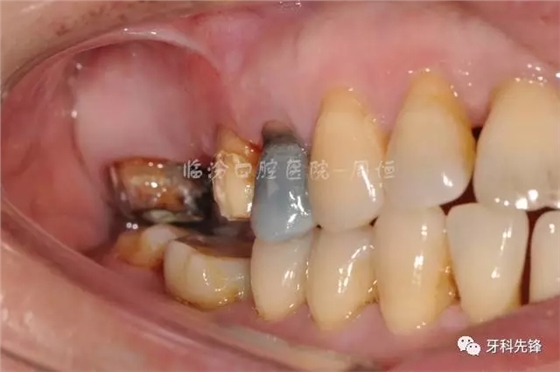

圖5拆除原修復(fù)體側(cè)位咬合照

640.webp (6).jpg